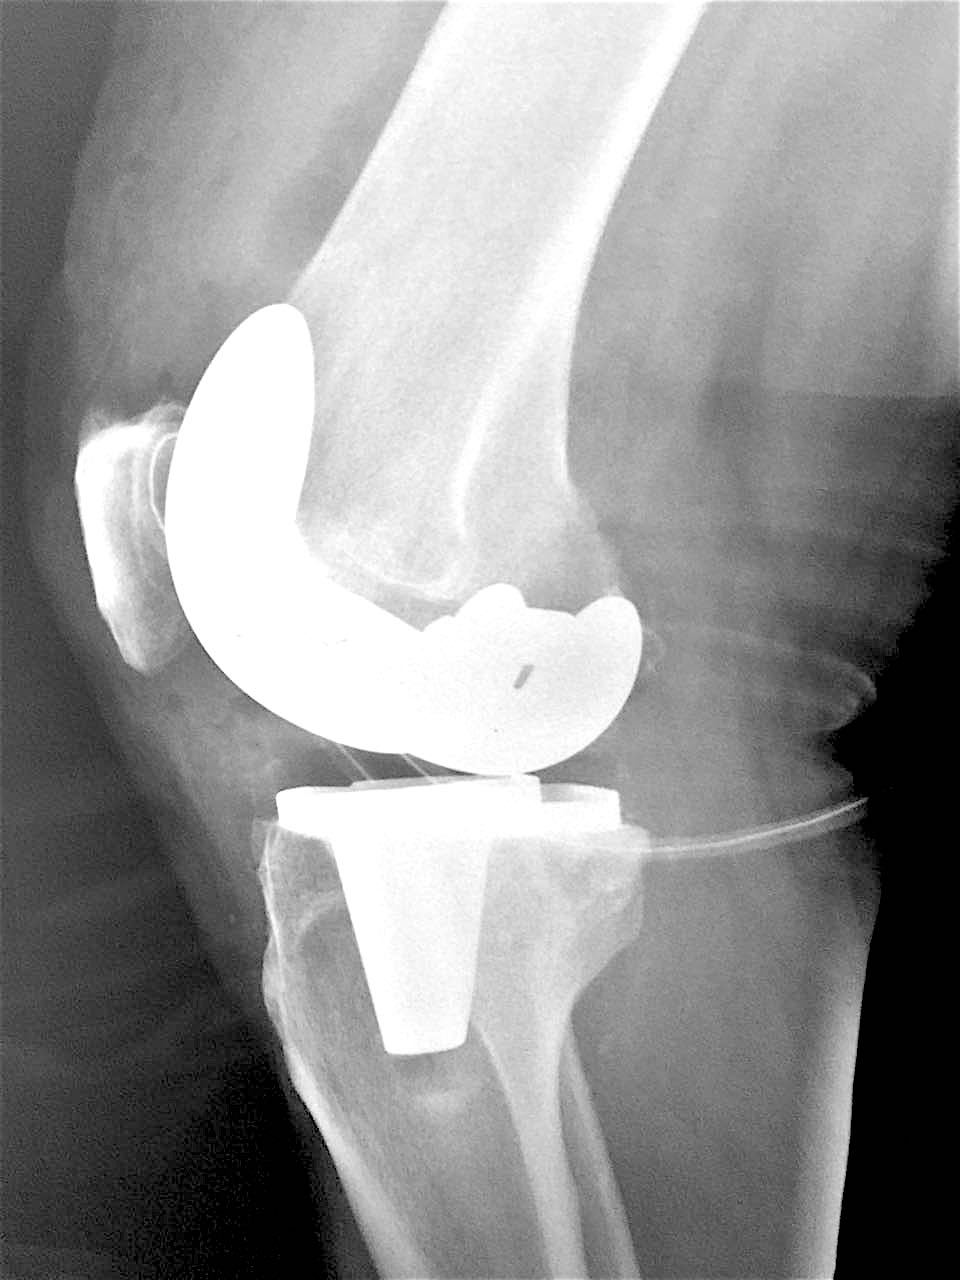

Сделано тотальное эндопротезирование коленного сустава, костная аллопластика материалом «Лиопласт».